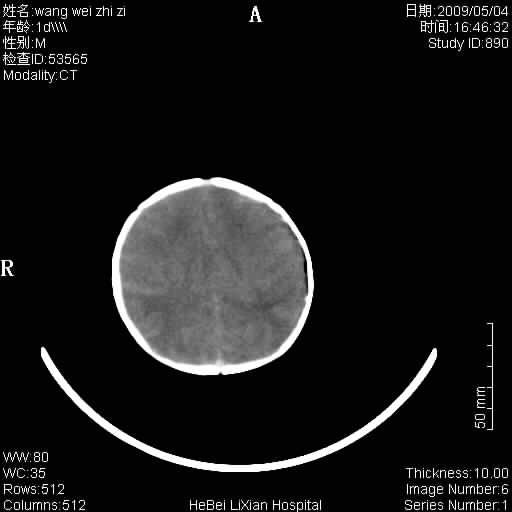

患者,男,1天,上肢抽动数次伴气促.有急产史.可以诊断珠网膜下腔出血吗?

局部5毫米薄层扫描